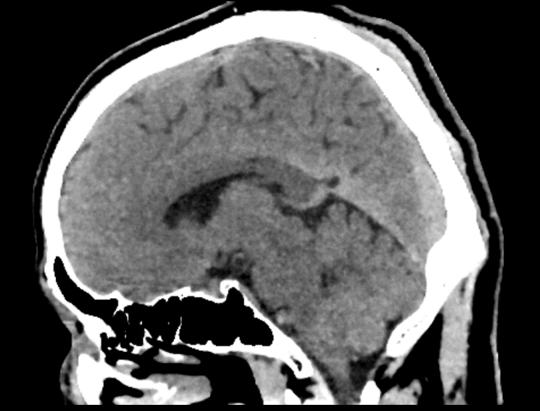

半秒单圈轴扫即可完成全脑扫描,多重软硬件技术克服锥束伪影和散射伪影挑战,提升软组织密度分辨率,改善颅底结构显示效果

3D打印精密工艺三维防散射栅格、Real 3D Full大锥角重建算法等多重硬件、软件技术协同,克服宽体探测器的核心技术挑战,天河640单圈扫描即可获得高质量的全脑、全冠脉轴扫图像